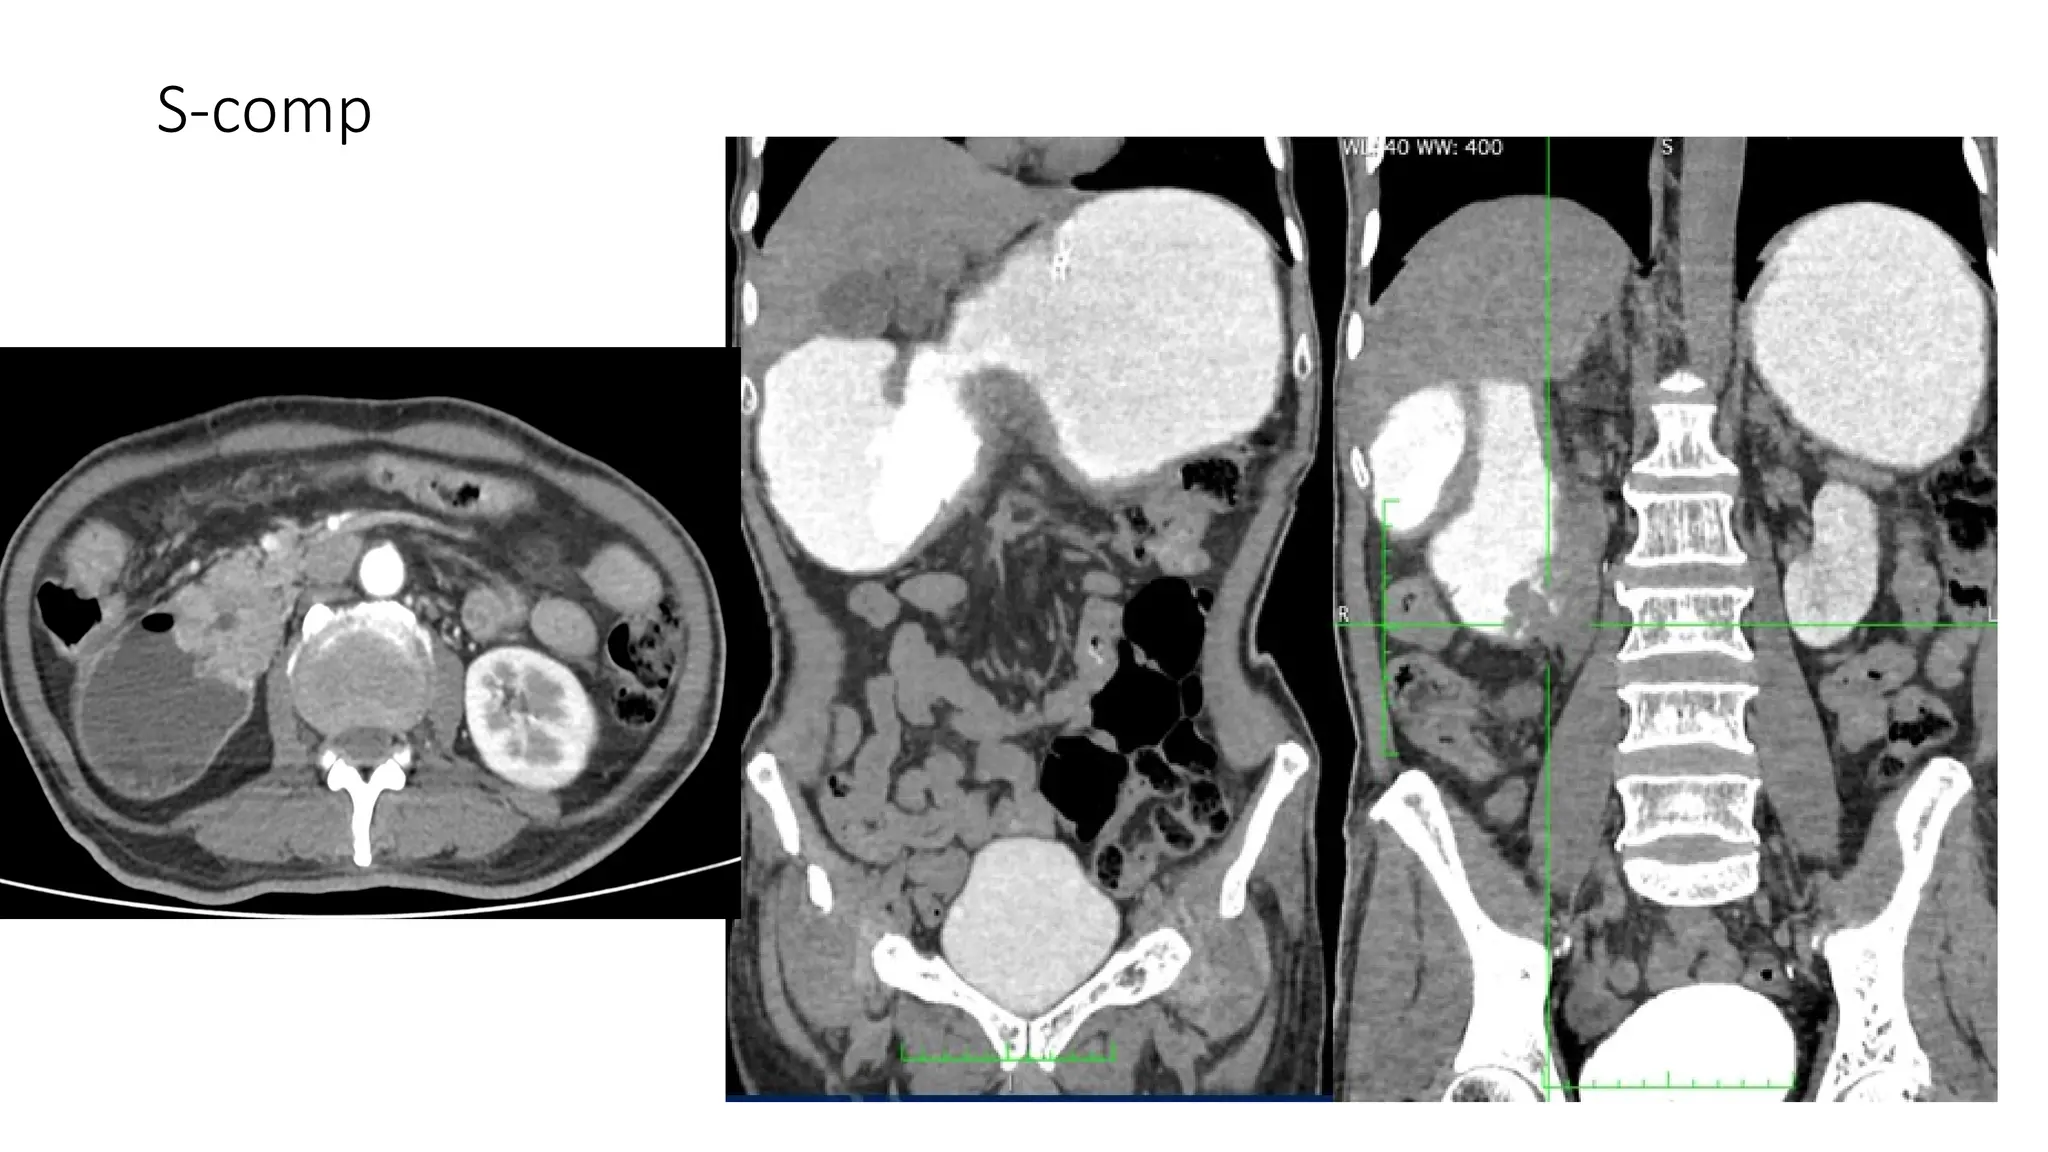

The document lists various components and classifications related to the gastro-intestinal system. It includes multiple codes and identifiers associated with different aspects of this biological system. The content appears to be a structured categorization rather than a narrative or descriptive text.